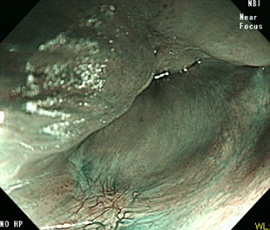

内視鏡画像(NBI)